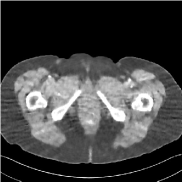

Refer to caption FBPRMSE = 194.09 HURefer to caption FBPRMSE = 194.09 HURefer to caption PWLS-ULTRARMSE = 43.40 HURefer to caption PWLS-ULTRARMSE = 43.40 HU

Refer to caption FBPConvNetRMSE = 34.24 HURefer to caption FBPConvNetRMSE = 34.24 HURefer to caption SUPER-FCN-DataTermRMSE = 31.21 HURefer to caption SUPER-FCN-DataTermRMSE = 31.21 HU

Refer to caption SUPER-FCN-ULTRARMSE = 28.82 HURefer to caption SUPER-FCN-ULTRARMSE = 28.82 HURefer to caption ReferenceRefer to caption Reference

Figure 5: Reconstructed images of slice 150 of patient L192 using of FBP, PWLS-ULTRA, FBPConvNet, SUPER-FCN-DataTerm, and SUPER-FCN-ULTRA, respectively, shown along with the reference.

Fig. 5 shows reconstructions using FBPConvNet, SUPER-FCN-DataTerm (i.e., β=μ=0𝛽𝜇0\beta=\mu=0), PWLS-ULTRA, and SUPER-FCN-ULTRA, respectively. For SUPER-FCN-DataTerm, when optimizing the data-fidelity term, we start with the deep network’s output and ran 5 iterations for the data-fidelity term to avoid overfitting to the analytical FBP images. In Fig. 5, obviously, FBPConvNet significantly suppresses noise and artifacts compared to PWLS-ULTRA, but it also over-smooths many details (e.g., features in the zoom-in box) in the reconstruction. SUPER-FCN-DataTerm, by enforcing data consistency, helps reduce overfitting issues and reconstructs image details and tissue boundaries better compared to the standalone FBPConvNet. Our SUPER-FCN-ULTRA method, however, exploits richer prior information (via the union of learned sparsifying transforms) and explicit network regularizer and outperforms the SUPER-FCN-DataTerm approach. Additional such comparisons for other selected test slices are included in the supplement (Fig. 15).